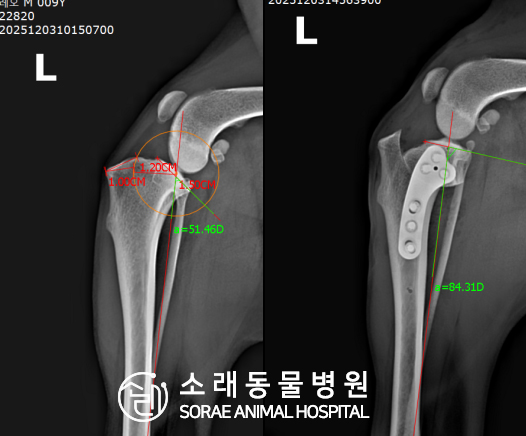

계산식으로 사전에 계획해두었던 플랜에 따라 경골을 절제하고

플레이트와 스크류를 사용하여 임플란트를 적용해 주었습니다.

반대 방향으로 밀려나 어긋나있던 대퇴골과 정강이가

제 자리를 찾으면서 무릎의 각도가 교정된 것을 확인할 수 있습니다